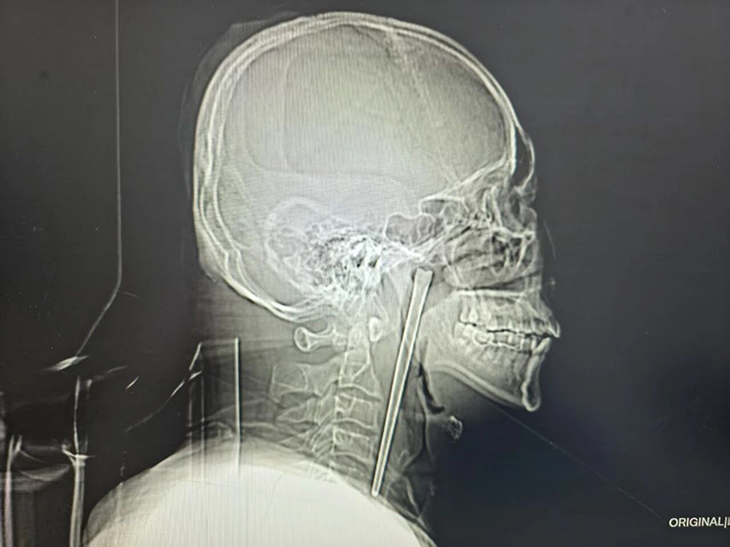

しかし、中国の遼寧省大連市に住むワンさん(46歳)の喉に刺さっていたのは、小骨などではなく「長さ12センチの金属製の箸」だった。しかも彼は、その状態のままなんと「8年間」も平然と日常生活を送っていたというのだ。

レントゲンを見た医師たちは、喉に真っ直ぐ刺さる12センチの金属棒に唖然としたが、彼から「8年前の箸だ」と聞いてさらに絶句したに違いない。

医師チームは首を切開せず、口の中から内視鏡を使って異物を取り出す「低侵襲手術」のプランを立案。執刀したファン・ウェイペン医師は、箸に絡みついた組織を慎重に剥がし、12センチのステンレス箸を無傷で(そしてワンさんの首も無傷で)引き抜くという神業を成し遂げた。